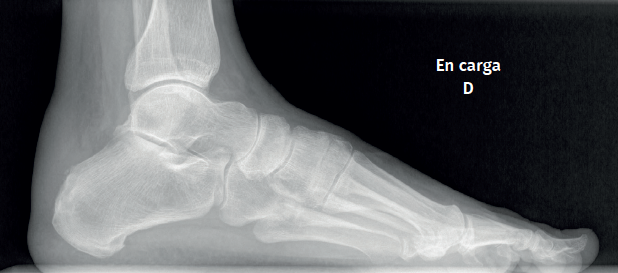

Plain radiography

The dorsoplantar and sagittal views of both feet under loading conditions are indicated, together with the posteroanterior view of the ankles under loading conditions.

Figure 3. Plain radiography, Sagittal view with weight-bearing. Moderate calcifications in the insertion of the Achilles tendon with intratendinous enthesophyte. Morphological alterations of the posterior tuberosity of the calcaneus.

Plain radiography under loading conditions is the essential initial diagnostic tool(20). It allows us to assess alignments and dysmetria, to measure angles, to determine the morphology of the calcaneus and its posterior tuberosity, to characterise bone exostosis and increments in thickness of the retrocalcaneal soft tissues, and to plan surgical procedures (Figure 3).